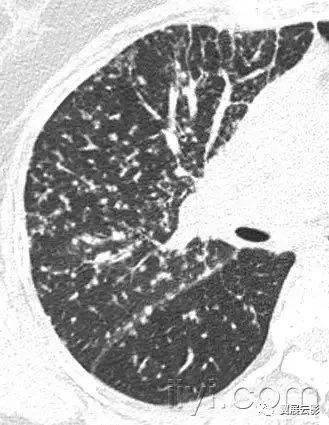

十九、肺实变:

病理学:肺实变是指渗出,或者其他疾病成分替代肺泡内气体,导致肺实变。

平片和CT:肺实变表现为肺实质密度的均匀一致性增高,导致肺血管和气道壁边缘不清。有时可见含气支气管征。只有在极少数的情况下,肺实变的密度变化有助于鉴别诊断,例如脂性肺炎是密度减低,胺碘酮中毒时密度增高。

图示为多灶性的肺实变。